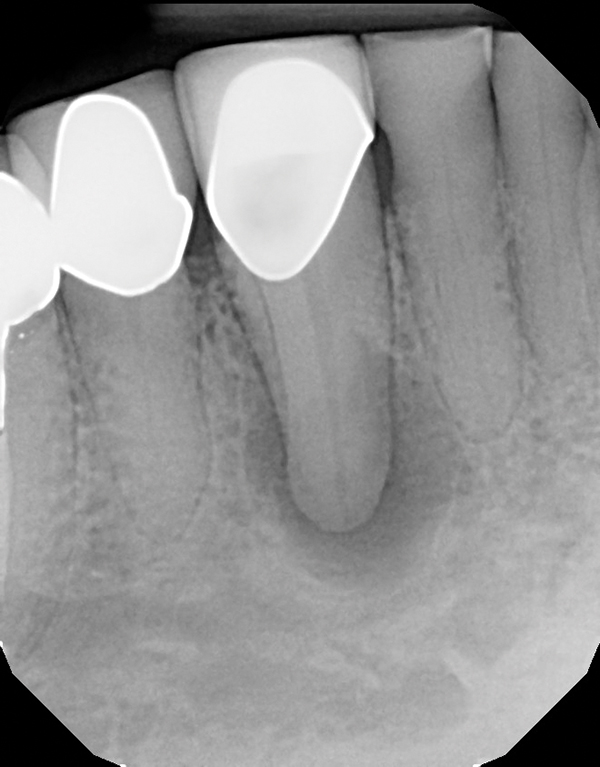

From rootcanaltreatment.blogspot.com

Endodontics Obturation with tooth having internal resorption. What Is Obturation In Dentistry Diwakar kinra, editorial director of de’s endo file, talks through. That is down to how well you clean the canal and eliminate bacteria. Learn about obturation from a clinician’s guide to clinical endodontics dental ce course & enrich your knowledge in oral healthcare field. There are many different obturation techniques; It’s not going to make or break successful treatment. No. What Is Obturation In Dentistry.